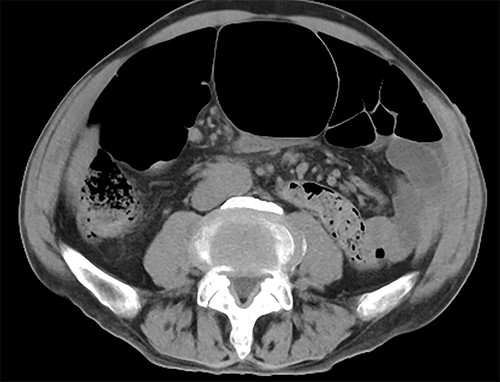

Endoscopic examination showed that the site of torsion was near the sigmoid rectum (Fig. 1), and a computed tomography(CT) scan revealed prominent dilatation of the oral bowel (Fig. 2).

CT findings. CT showed dilation of the oral intestinal tract was observed.